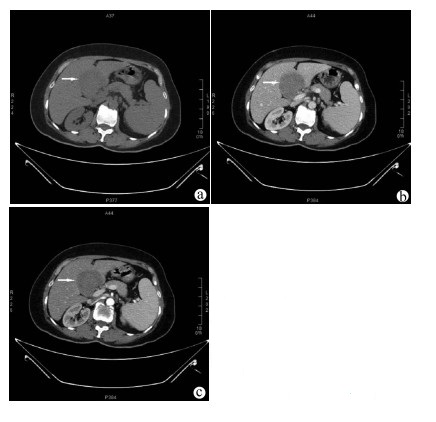

原发性肝淋巴瘤伴贫血和低蛋白血症1例报告

2021, 37(8): 1911-1913. DOI: 10.3969/j.issn.1001-5256.2021.08.034

摘要(963) HTML (226) PDF (2390KB)(53)

摘要: